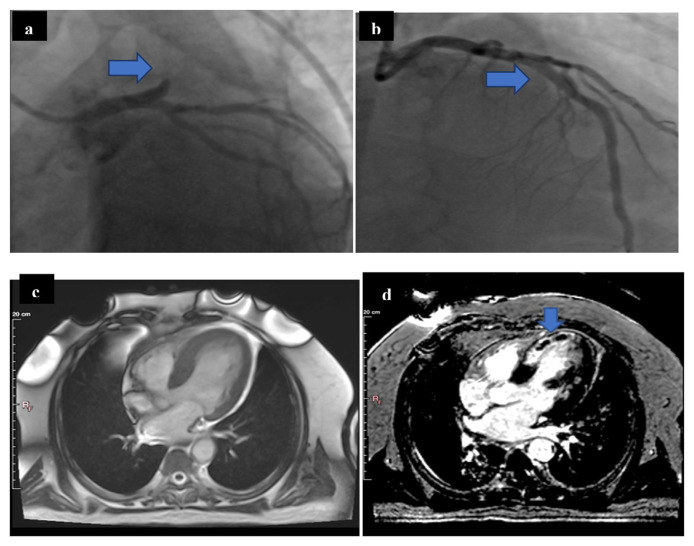

Methods: Ninety-three patients with heavy thrombus burden were enrolled in this study; sixty-five patients met our inclusion criteria. After failed trial of restore the artery patency, aspiration thrombectomy was done followed by PCI for thirty-one patients (aspiration group), while conventional PCI without aspiration thrombectomy was performed for 34 patients (conventional group). The primary end points were both occurrence and extent of microvascular obstruction (MVO) evaluated mainly by CMR, in addition to angiographic data (MBG and TIMI flow grade).

Results: The incidence of microvascular obstruction (MVO) was significantly higher in conventional group (18 patients, 52.9 %) when compared with aspiration group (7 patients, 22.6 %; p-value = 0.012). Moreover, significant differences existed between the studied groups regarding MVO extent. For instance, MVO extended to >4 segments in only 3 patients (9.7 %) in aspiration group, but in 13 patients in conventional group (38.2 %; p-value = 0.007).

Conclusions: Aspiration thrombectomy substantially reduces both the incidence and extent of microvascular obstruction as an adjunctive technique to PPCI in STEMI patients with heavy thrombus burden.